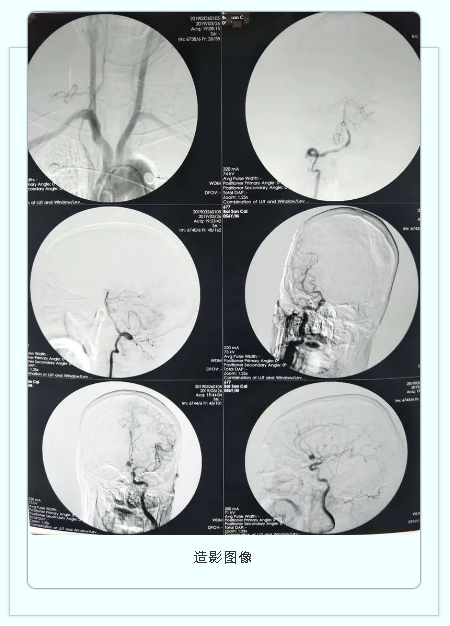

神经外科二病区独立完成首例全脑血管造影术

3月26日下午,神经外科二病区成功开展了院内首例全脑血管造影术,标志着我院在脑血管疾病诊治取得新突破。

神经外科二病区主任康宏达带领冉军民、姜正辕医师第一时间在DSA(数字血管造影机)下实施脑血管造影手术检查,明确了患者系前交通动脉瘤破裂出血。手术非常顺利,术后患者无不适。

该例脑血管造影术的成功实施,对我院神经外科的发展具有里程碑意义,也将为全市广大人民的健康带来新的福音。正如康宏达主任所说:“我们有信心,也有能力在造影技术上实现跨越式发展,更好的服务人民群众。”